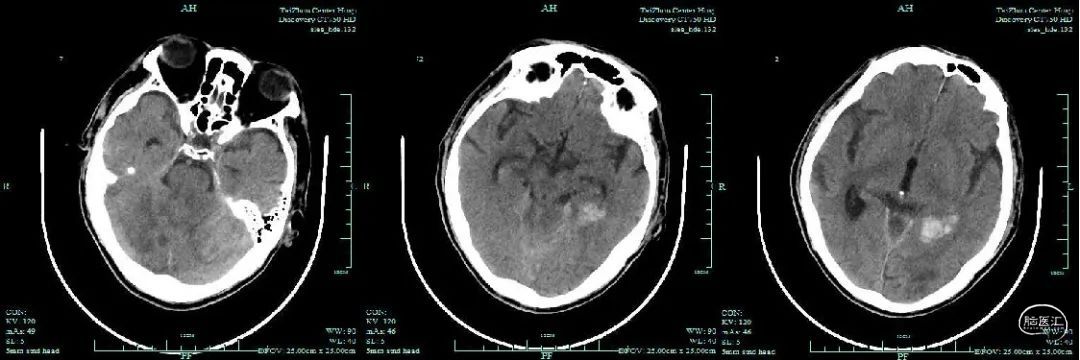

术后3d头颅CT